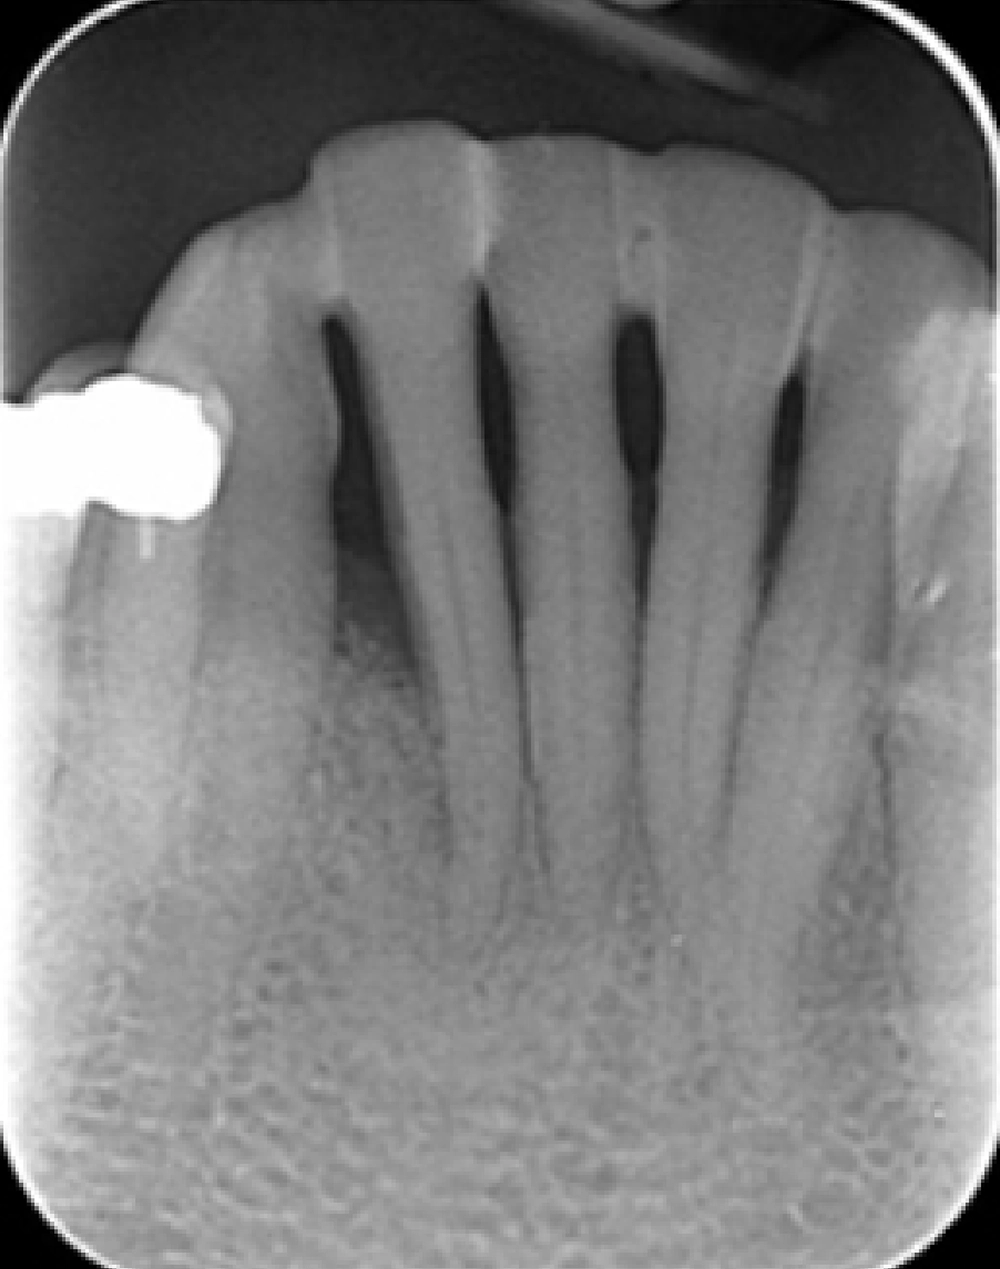

Before

Periodontal disease, if left untreated, can lead to significant damage to the gums, bone, and deeper supporting structures of the teeth. Periodontal regeneration is a surgical treatment focused on reversing this damage by stimulating the natural healing potential of the body. This advanced procedure repairs periodontal tissue damage, including lost bone and gum, through the use of proven techniques and materials such as grafts and regenerative proteins.